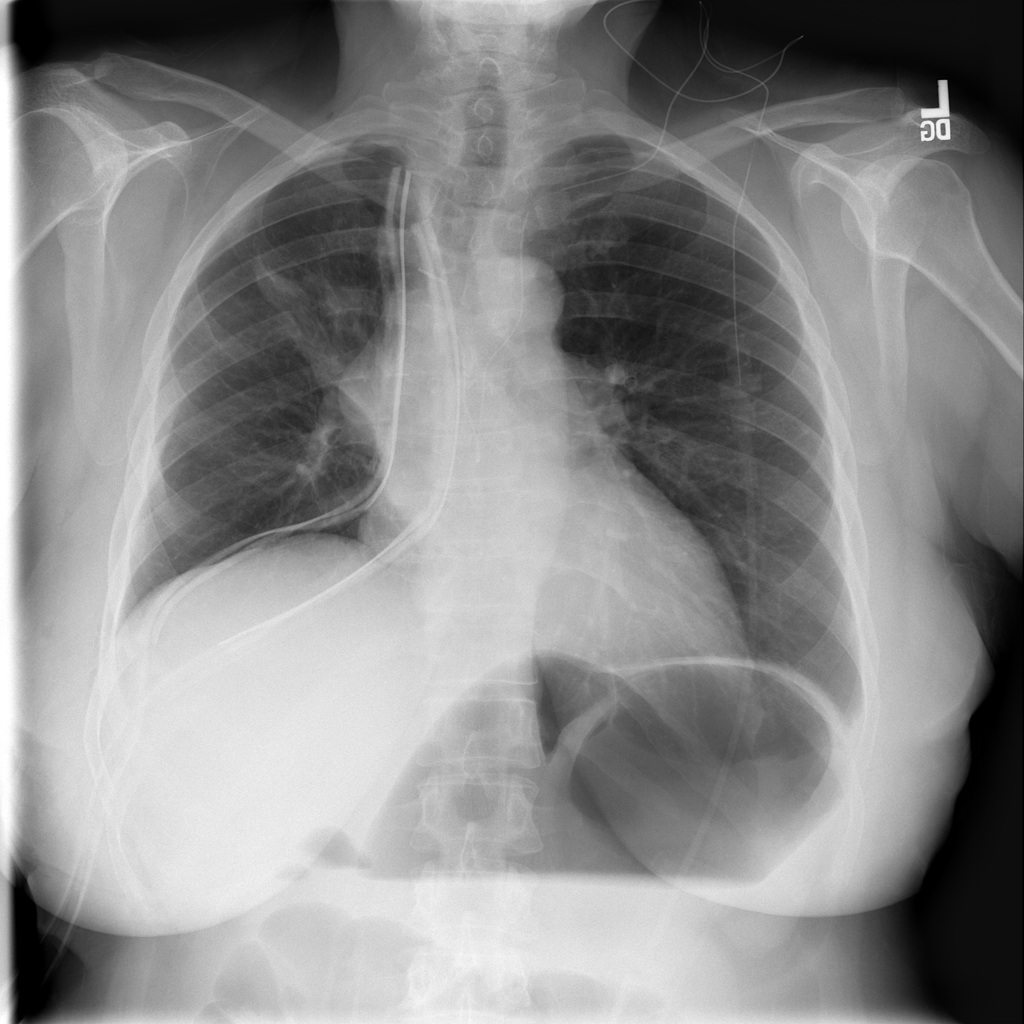

PAT-4639 · IMG-013Pneumothorax

PAT-4639 · IMG-013

AP